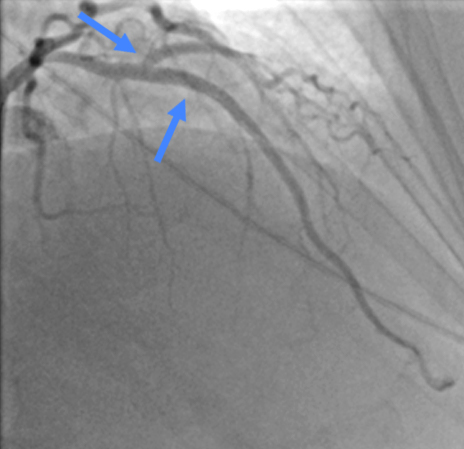

После проведения стентирования ПМЖА было выполнено повторное определение моментального резерва кровотока в ПМЖА и ДА и получены значения 0,96 в ПМЖА и 0,95 в ДА, соответственно. Эти данные указывают на то, что стентирование ПМЖА было выполнено адекватно, а поражение устья ДА является гемодинамически незначимым и в стентировании не нуждается.